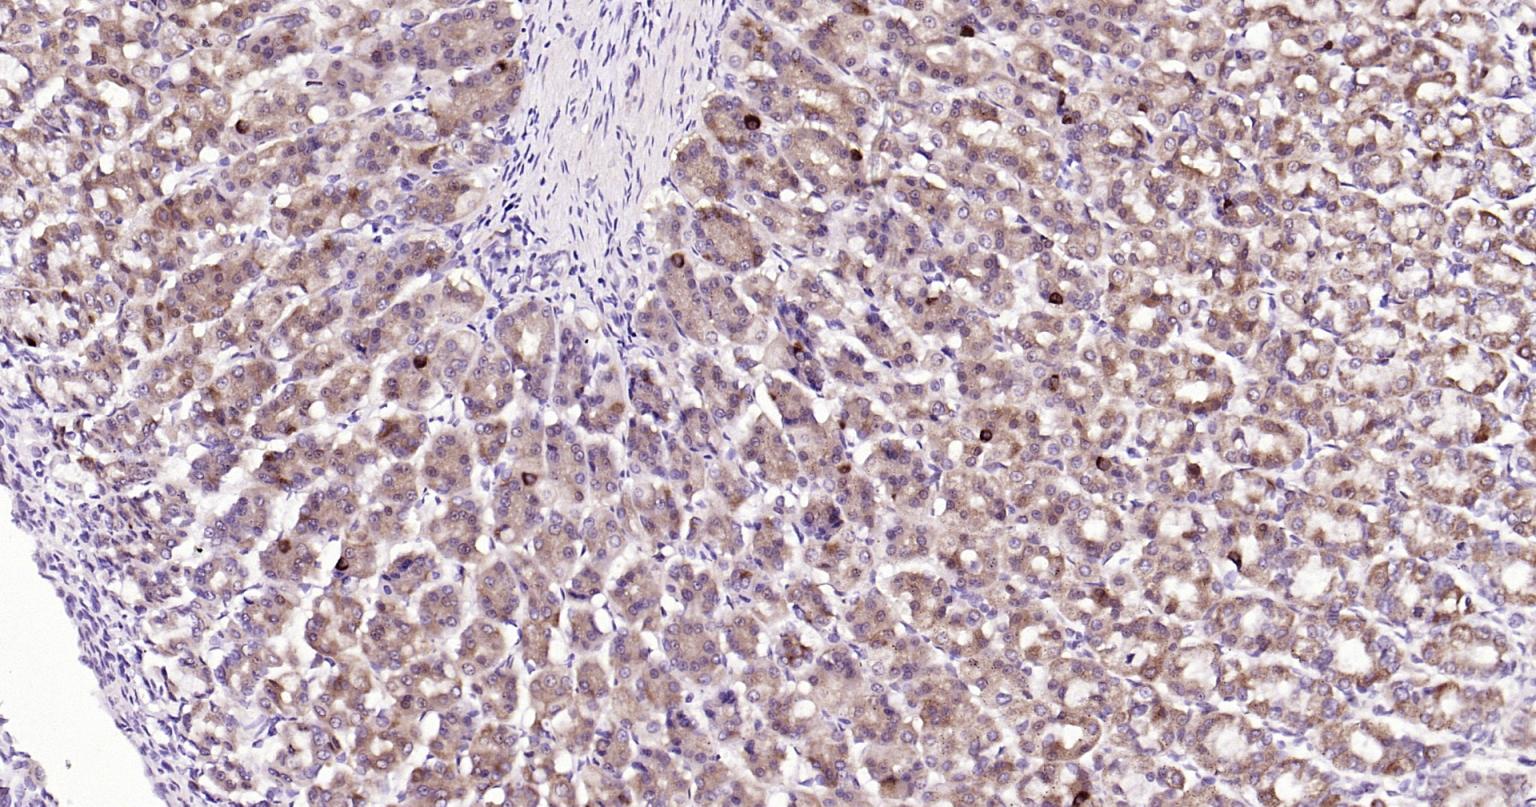

| IHC-P | Human, Mouse, Rat | Rabbit | 1:400-800 |